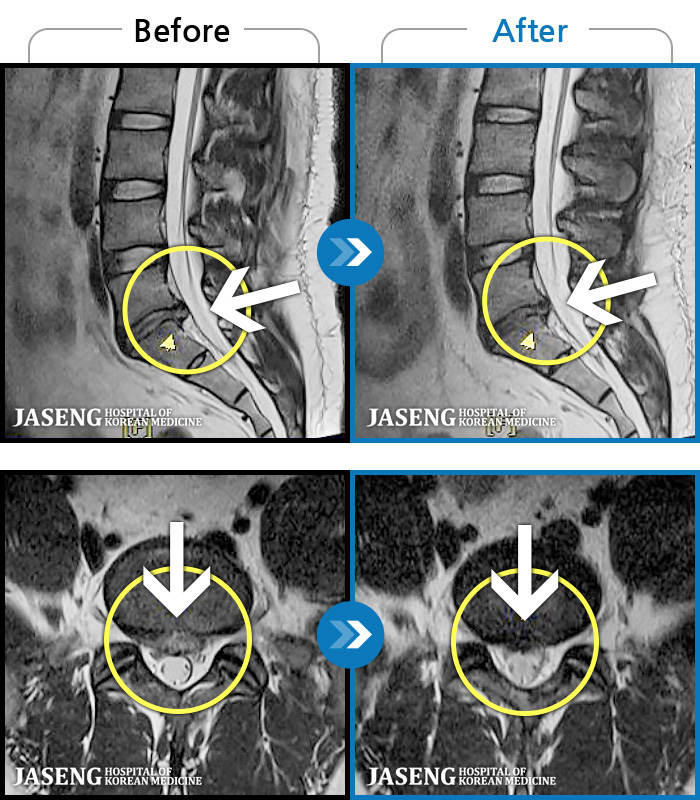

97 MRI ũ ʸ Ȯϼ.

ȯںп Ǹ ǿ ԿǾ, ο ġ ۿ Ƿ ġḦ Ͻñ ٶϴ.